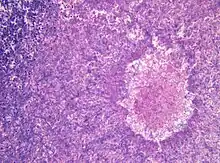

| Aspergillomas complicating tuberculosis: multiple aspergillomas within large cavitary lesions of tuberculous origin. | |

Although most fungi—and especially Aspergillus—fail to grow in healthy human tissue, significant growth may occur in people whose adaptive immune system is compromised, such as those with chronic granulomatous disease, who are undergoing chemotherapy, or who have recently undergone a bone marrow transplantation. Within the lungs of such individuals, the fungal hyphae spread out as a spherical growth. With the restoration of normal defense mechanisms, neutrophils and lymphocytes are attracted to the edge of the spherical fungal growth where they lyse, releasing tissue-digesting enzymes as a normal function. A sphere of the infected lung is thus cleaved from the adjacent lung. This sphere flops around in the resulting cavity and is recognized on x-ray as a fungus ball. This process is beneficial as a potentially serious invasive fungal infection is converted into surface colonization. Although the fungus is inactivated in the process, surgeons may choose to operate to reduce the possibility of bleeding. Microscopic examination of surgically removed recently formed fungus balls clearly shows a sphere of dead lung containing fungal hyphae. Microscopic examination of older lesions reveals mummified tissue which may reveal faint residual lung or hyphal structures.[5]